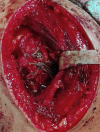

Irreducible shoulder dislocation is an uncommon event. When it does occur, blocks to reduction can include bone, labrum, rotator cuff musculature, or tendon. Concomitant rotator cuff tear at the time of initial dislocation is not an exclusive complication of anterior shoulder dislocation in the older population. Indeed, rotator cuff tear should not be excluded based solely on the patient's age. Rotator cuff interposition is not an uncommon complication after anterior dislocation of the shoulder. It should be suspected when there is incongruency of the joint and persistent subluxation on postreduction radiographs. If such incongruence or subluxation is seen, a computed tomographic (CT) or magnetic resonance imaging (MRI) scan must then be obtained to determine the nature of the interposed soft tissues. The key to treatment is early diagnosis and adequate imaging. Open reduction and repair of the rotator cuff should be performed. We present a technique for treating irreducible anterior shoulder dislocation caused by interposition of the subscapularis tendon. Both CT and MRI observations, along with intraoperative findings and surgical technique, are discussed.